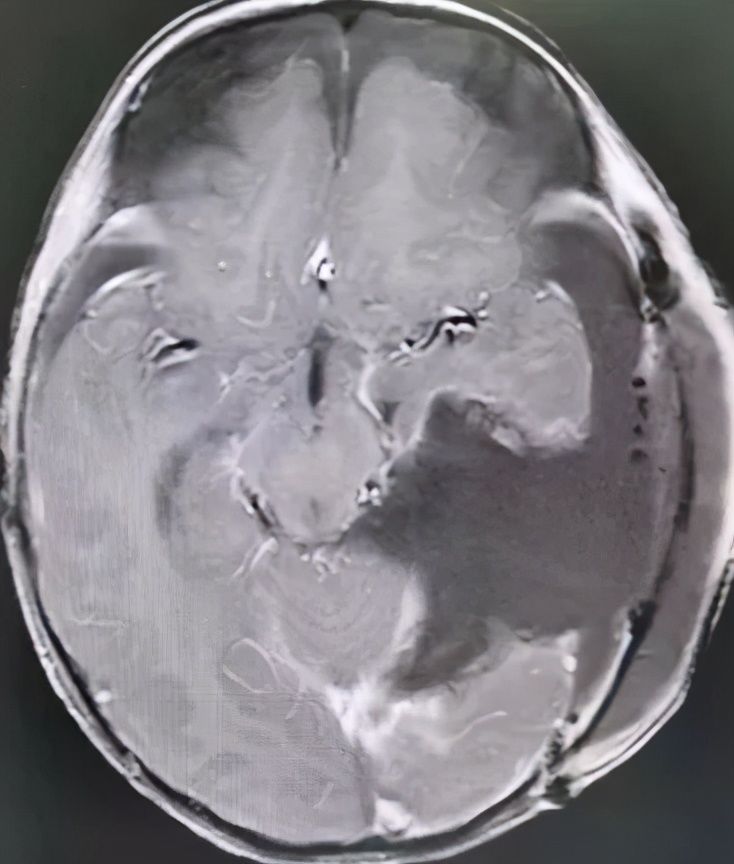

术后MR显示:肿瘤被全切除,脑干也复位了